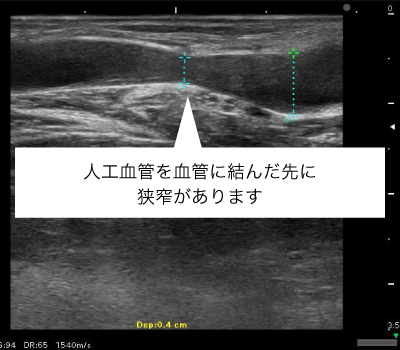

シャントや人工血管の狭くなったりつまったりした部分を血管内から風船で拡張することでシャントや人工血管を改善する手術です。

局所麻酔をした上で、シャントや人工血管に「シース」という透析使用と同程度の太さの針を刺します。シースから狭くなっている部分にカテーテルをすすめ、バルーンカテーテル(風船)によって異常がある部位を血管の内側から広げます。

先端にバルーンのついたカテーテルをシャント血管内に挿入し、シャント血管が細くなっている場所までカテーテルを進め、バルーンを膨らませてシャント血管を拡げます。